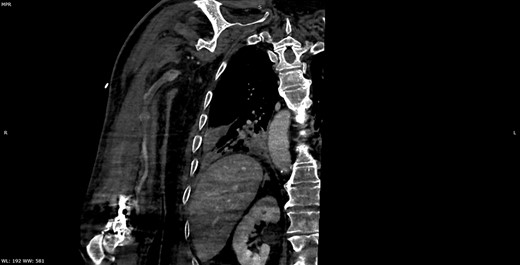

Seven days later, while his general condition was deteriorating, he developed acute ischemia in his right thumb and index finger (Fig. 2). In the ipsilateral forearm, a radial artery catheter had been inserted for monitoring. An urgent radial artery embolectomy was performed and restored the arterial supply to the right hand. The antithrombotic agent was changed to fondaparinux (7.5 mg/once daily). However, within the next few days, it was clinically evident that the revascularization effort was unsuccessful as the thumb and index finger developed dry gangrene. On examination, there was no palpable radial pulse, the ulnar artery pulse was palpable at the level of the wrist and the capillary refill time was normal at the middle, ring and little fingers. A CT angiography (Figs 3 and 4) was performed, demonstrating complete thrombosis of the radial artery beginning at the level of the elbow as well as a 70% occlusion of the ulnar artery ~15 cm proximal to the wrist. Thrombosis of the right axillary vein was also seen (Fig. 5). Orthopedic review was requested for consideration for finger amputation with a recommendation for arm amputation at the level of the elbow. Unfortunately, the patient died 72 h later from respiratory failure following a 24-day admission in ICU.

Multiplanar reformation image shows severe near occlusion 6-mm stenosis of the ulnar artery.